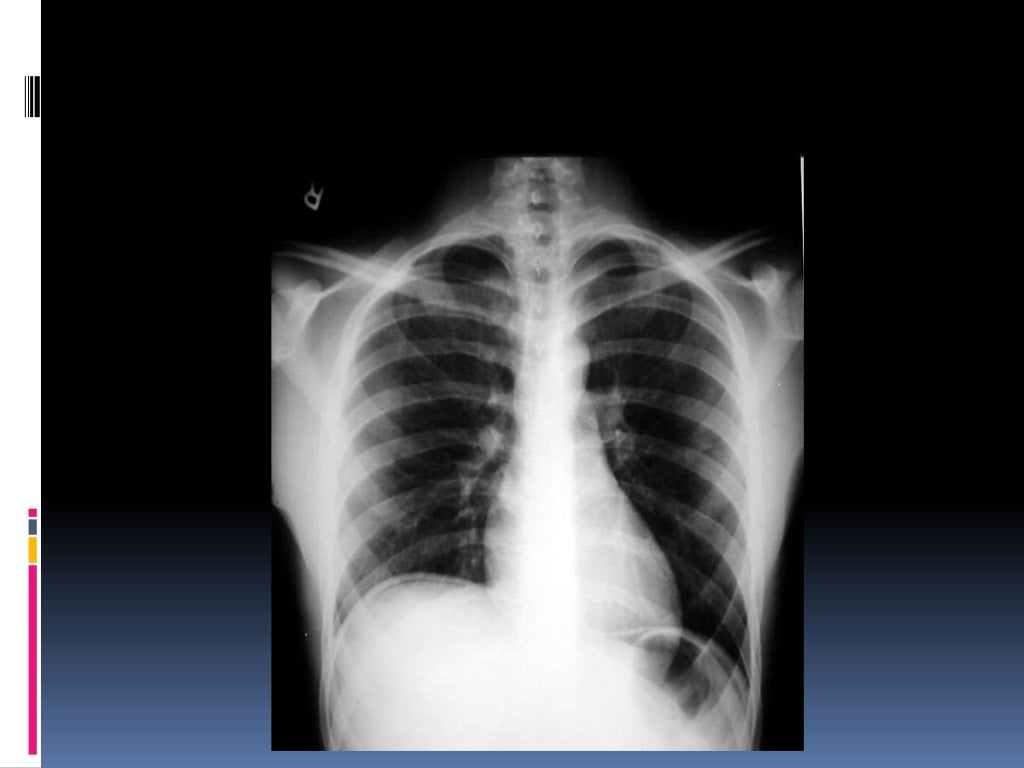

Normal Chest X Ray Images

Repeated Chest Xray. (Normal chest Xray). Download Scientific Diagram Normal Chest X Ray Slideshare It outlines key views (pa, ap, lateral), proper positioning, and critical structures to examine including the. How do you look at chest x ray? Lesions or fractures * soft tissue ; It outlines the key factors to consider, including orientation, inspiration, penetration, and rotation. Common abnormalities such as pneumonia, effusions, pneumothorax, and masses are described. It outlines the key areas. Normal Chest X Ray Slideshare.

Normal chest Xray on admission Download Scientific Diagram Normal Chest X Ray Slideshare It outlines key views (pa, ap, lateral), proper positioning, and critical structures to examine including the. It outlines the key areas to examine, including the trachea, mediastinum, heart, diaphragm,. Common abnormalities such as pneumonia, effusions, pneumothorax, and masses are described. It outlines the key factors to consider, including orientation, inspiration, penetration, and rotation. How do you look at chest x. Normal Chest X Ray Slideshare.